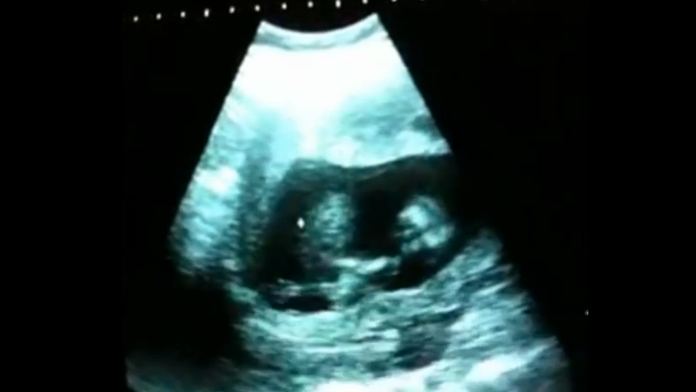

Skvelá tanečníčka! A to sa ešte ani nenarodila

To, čo v tehotenskom brušku vystrája táto nezbednica vás zaručene pobaví.

Každá žena by mala počas tehotenstva absolvovať ultrazvulk, aby sa vedelo, či je s plodom všetko v poriadku. Tak urobil aj tento šťastný pár. Nečakali však, že ich vytúžené dievčatko je až takáto huncútka. A ešte aj s talentom!

Hoci niektoré bábätká v brušku vedia narobiť tiakisto veľkú šou, toto dievčatko sa vie zabávať skutočne jedinečným spôsobom. Údajne to svedčí o tom, že je šťastná a zdravá. Video pripravil portál Dobré noviny a za krátky čas sa stihlo stať hitom internetu. Pozrite si jej šantenie aj vy.